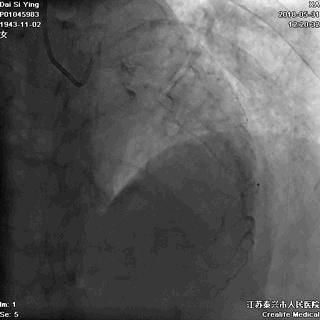

病例一 :79岁的老年女性,近期频繁出现胸口闷痛,休息后稍微缓解,一直没在意。一早晨突发胸痛,比前几日都要严重,老奶奶以为和往常一样,休息观察就可以了,就没想到到医院去。结果几个小时过去了,发现已经不能呼吸,胸痛越来越重,遂打120前往医院。到了医院急诊造影,发现心脏冠脉已经发生闭塞,随后立即安排了急诊手术。好在手术很成功,但是因为缺血时间过久,心肌发生了不可逆的损害,导致老奶奶今后的生活质量严重下降。

血管闭塞

该患者因为之前出现胸闷胸痛,而休息后缓解,老奶奶就认为没有异常,其实这个时候已经发生了心脏冠脉的轻微闭塞,出现了轻微的临床症状,也可以说是心梗前的征兆。但是,随着时间的推移,血管闭塞越发严重,导致心肌大面积缺血。